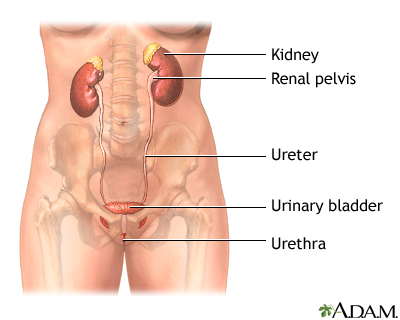

The urethra is a tube connected to the bladder. Urine is held in the bladder until it becomes full and then it travels through the urethral opening to be released from the body. Its anatomy is different in men and women. One of the most common differences is that men have longer urethras than do women. Possible problems can include pain, infections, and cancer.

Generally, all humans have urethras. In men, the structure is part of the reproductive system. Located in the penis, it transports urine and semen from the body. This tube in males typically measures about eight inches (about 20.3 cm) long.

In women, the urethra generally is about 1.5 inches (about 3.8 cm) long. Unlike males, it is not part of the female reproductive system. Instead, it is located above the opening of the vagina, within the labia minora. Its only purpose in women is to serve as an exit site for urine.

In women, the urethra generally is about 1.5 inches (about 3.8 cm) long. Unlike males, it is not part of the female reproductive system. Instead, it is located above the opening of the vagina, within the labia minora. Its only purpose in women is to serve as an exit site for urine.

This tube in males typically measures about eight inches (about 20.3 cm) long. An enlarged prostate may be a symptom of urethral strictures. In women, the urethra generally is about 1.5 inches (about 3.8 cm) long. Unlike males, it is not part of the female reproductive system.